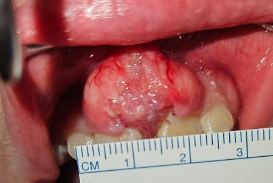

Figure 2: One of the gingival lesions, initially diagnosed as squamous papilloma on initial biopsy